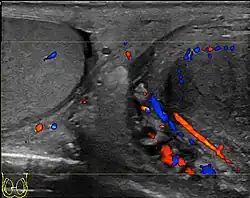

At ultrasound, the findings of acute epididymitis include an enlarged hypoechoic or hyperechoic (presumably secondary to hemorrhage) epididymis [Fig. 20a]. Other signs of inflammation such as increased vascularity, reactive hydrocele, pyocele and scrotal wall thickening may also be present. Testicular involvement is confirmed by the presence of testicular enlargement and an inhomogeneous echotexture. Hypervascularity on color Doppler images [Fig. 20b] is a well-established diagnostic criterion and may be the only imaging finding of epididymo-orchitis in some men.

Doppler ultrasound of epididymitis, seen as a substantial increase in blood flow in the left epididymis (top image), while it is normal in the right (bottom image). The thickness of the epididymis (between yellow crosses) is only slightly increased (7 mm). -

Doppler ultrasound of the scrotum of the same case, in the axial plane, showing orchitis (as part of epididymo-orchitis) as hypoechogenic and slightly heterogenic left testicular tissue (right in image), with an increased blood flow. There is also swelling of peritesticular tissue.